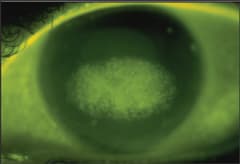

The presence of a central smudge, haze or significant pellicle (Figure 3) is an indication that you need to retrain the patient on proper lens cleaning. This is an opportunity to emphasize to patients that cleaning of the posterior surface of the lens will help them maintain clear, comfortable vision without episodes of pain and disrupted wear.

Figure 3. A corneal reshaping lens with significant pellicle formation.